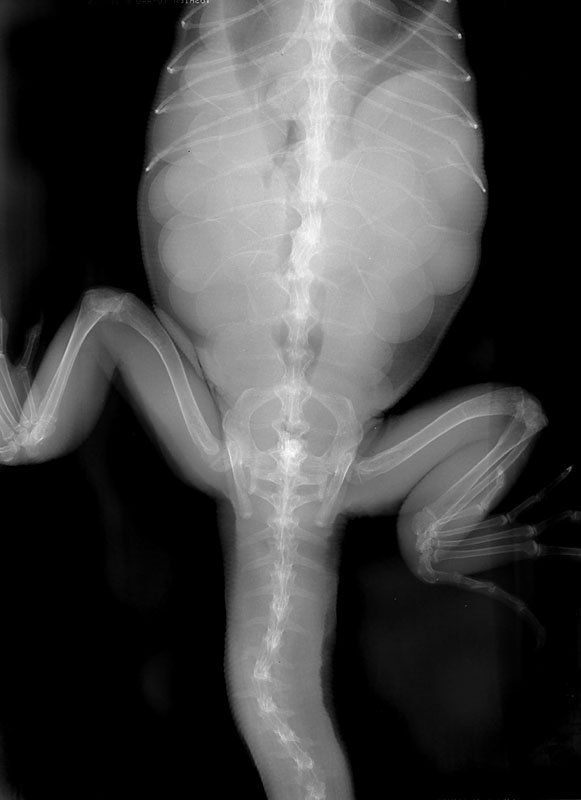

卵胞は卵巣から卵管に排卵されます。卵では次第に卵殻が形成されます。卵殻がある卵は絶対に吸収することはありません。

卵殻はX線にうつりますが、トカゲの卵殻は薄いのが普通なので明確にはうつりません。

卵殻が形成された卵を持ったイグアナが無事に産卵させるために、産卵場所を設けます。不適切な産卵環境であると産卵できずに、卵塞を起こす可能性が高くなります。産卵する場所は具体的に産卵箱を使用し、トカゲでは箱の横に小さな入口を設け、湿度を保つために容器の半分くらいに湿らせたバーミキュライトか水苔などの床敷を産卵床として敷きます。産卵箱がダンボールなどで体の大きさに合わせて作ってあげるとよいです。